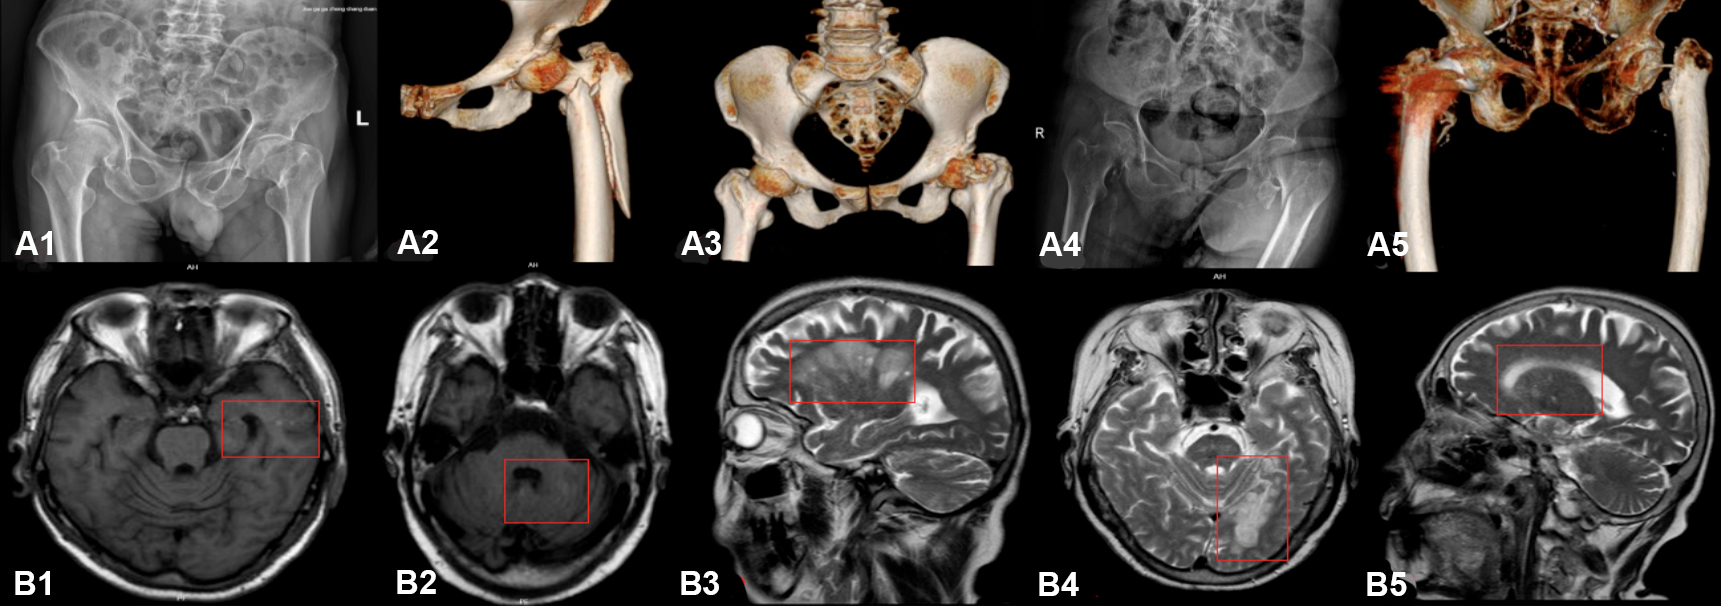

Herein, the authors describe an important yet under-recognised clinical phenomenon. Since 2024, five elderly patients with hip fractures (Figure A1-A5) were admitted for examination and incidentally diagnosed with new-onset acute/subacute silent CIs. Three patients had a history of CI (one of whom also exhibited delirium symptoms), one patient had no history of CI but presented with delirium, and one patient had a history of head trauma accompanied by headache. To comprehensively evaluate the surgical risks, the authors conducted cranial MR examinations for all five patients. Since none of the five patients exhibited clinical signs of acute CI within 27 hours post-injury, yet magnetic resonance imaging (MRI) revealed acute or subacute CI, these cases were classified as silent cases. Key patient characteristics included ages ranging from 62 to 92 years (average 79 years); four females and one male, and three patients had a history of stroke (Table I). All fractures were attributed to low-energy traumas, such as falls during ambulation. Cases involving falls secondary to transient cerebral ischaemia, syncope, or other related conditions were excluded from the analysis. Brain MRI confirmed new-onset infarcts without acute neurological deficits (Figure B1-B5). The four new infarct foci were small vessel lesions (diameter <10 mm), located in the periventricular region (two cases), cerebellar region (two cases), and thalamic region (one case). None of the patients exhibited signs of hypotension. One patient underwent artificial femoral head replacement; another received closed reduction and intramedullary nail fixation for an intertrochanteric fracture, and the remaining three were managed non-surgically. One surgical and one non-surgical patient developed delirium, and another patient experienced recurrent symptomatic stroke within one week. These findings indicate that hip fractures may act as a stress event triggering cerebral ischaemia, revealing potential blind spots in the existing perioperative assessment system.5

Figure 1: Imaging characteristics of fractures (A1-A5) and cerebral infarctions (B1-B5) in five patients.